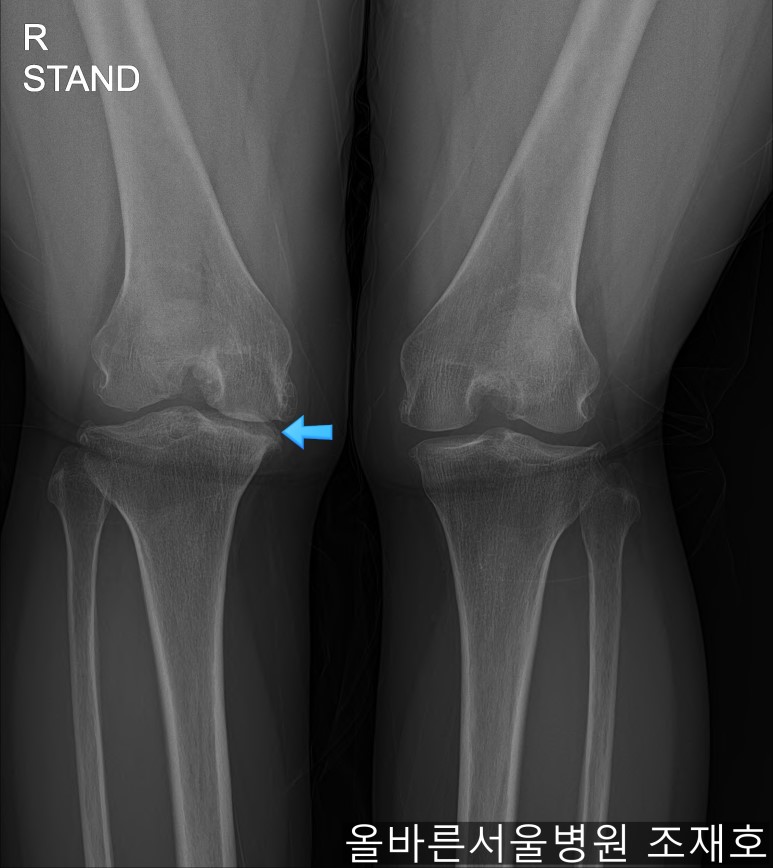

仅通过放射线片子观察到:右膝由于炎症严重,内侧胫骨及股骨已接触在一起,向内测严重变形。

左膝虽然也观察到了炎症,但远不如右膝严重。

如果通过X光片也观察到相同的病症,可以判断内侧关节的软骨大部分都损伤了。

观察膝盖下肢排列的扫描图像可看到右腿严重变形,身体中心向内倾斜。

这种状态下原本打算在其他医院做人工关节置换,后又到我院接受治疗。